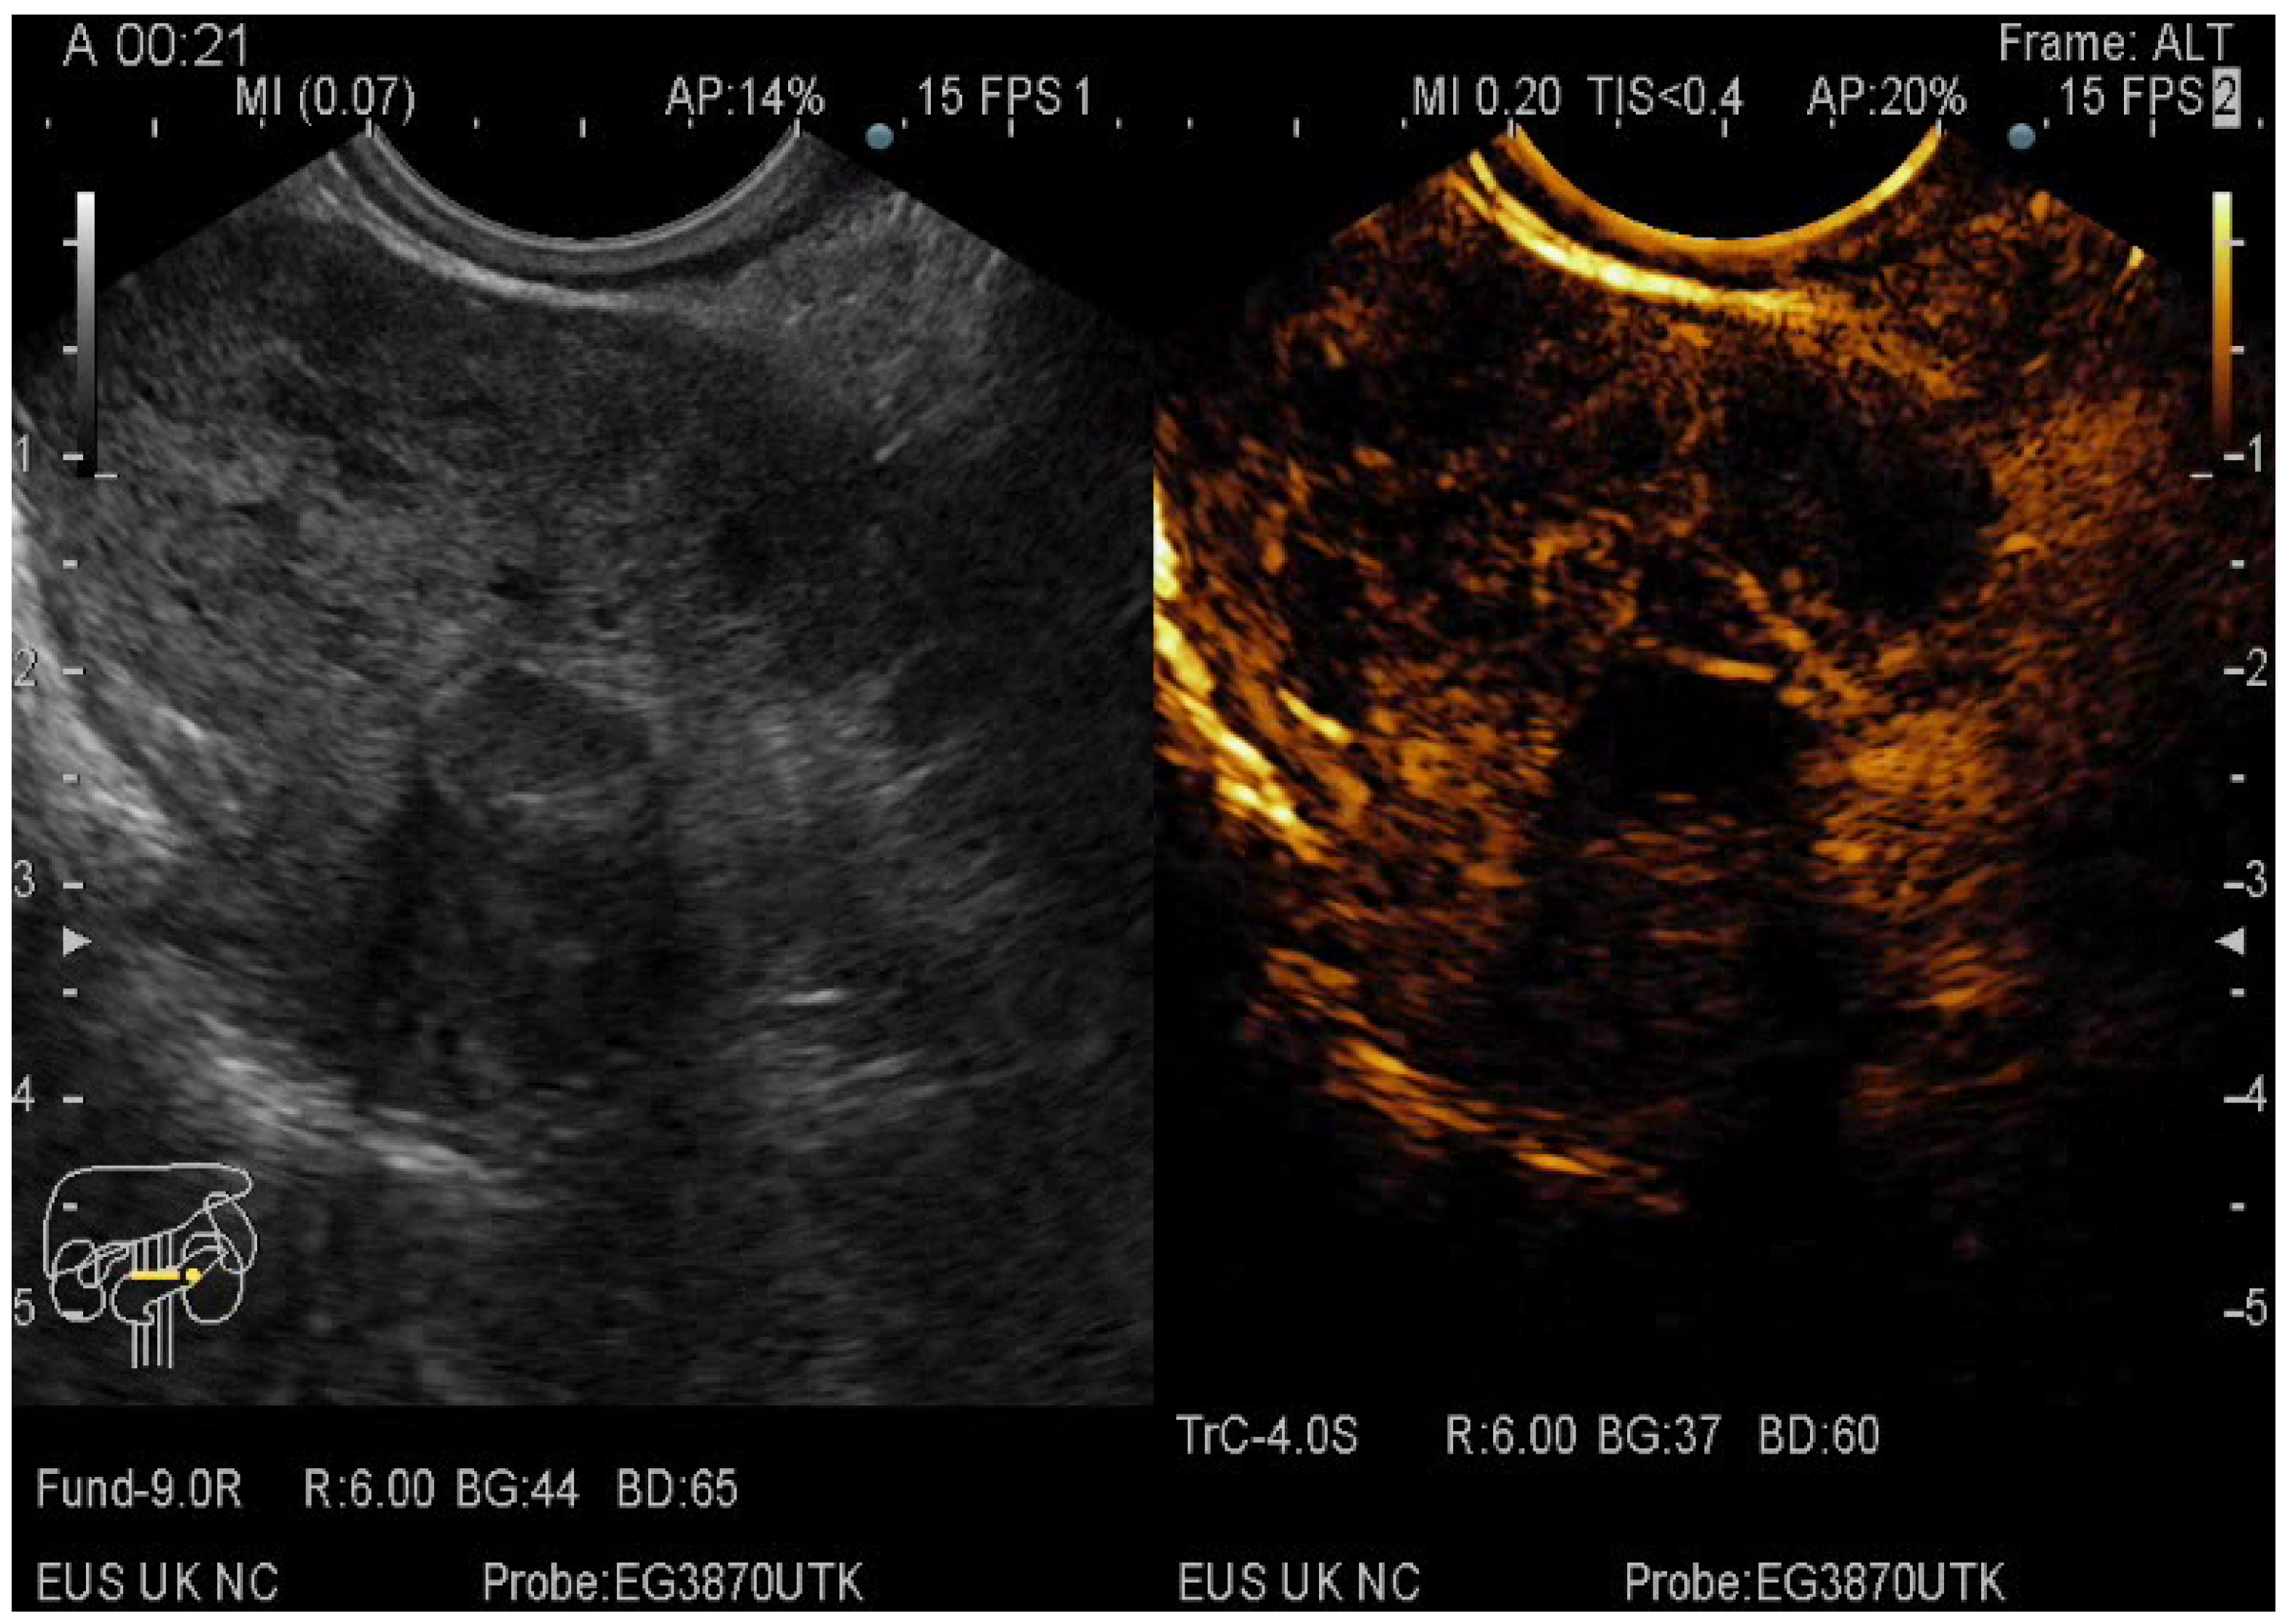

The pancreatic masses where located as it follows: 2/3 at the head level and 1/3 at the level of the body and tail. The size of the pancreatic masses ranged from 10 to 78 mm, with an average diameter of 35 mm. For obtaining the core tissue, fanning technique was applied with a mean number of needle passes of 2 and a range from 2 to 5 passes. Final pathology revealed pancreatic ductal adenocarcinoma–PDAC (149) (Figure 3), mass-forming pancreatitis–MFP (57) (Figure 4), pancreatic neuroendocrine tumors–pNETs (23) (Figure 5 and Figure 6), undifferentiated carcinoma (17), mucinous carcinoma (5), and pancreatic metastasis (5).

Figure 6.

CE-EUS image of a pNEC (pancreatic neuroendocrine carcinoma) with aspect in the arterial phase and wash-out in the venous phase.

In 48% of the cases, the pancreatic lesion was described as hypoenhancing, with a final diagnosis of malignancy. Regarding the enhancement patterns, hypovascularity in both arterial and venous phase was associated with PDAC, hypervascularity or isovascularity in both phases were associated with either MFP or NETs, whereas the carcinomas were hypervascular (Table 6). A heterogeneous appearance with non-enhancing areas was noted in a small percentage of the hypoenhancing lesions and it might suggest necrosis. The overall diagnostic accuracy was 91%.